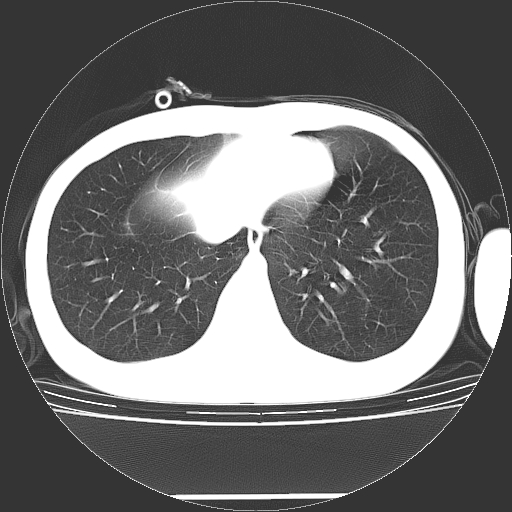

标题: CT19767:男,20岁,右侧气胸行闭式引流术后五天CT检查。 [打印本页]

男,20岁,右侧气胸行闭式引流术后五天ct检查看肺内是否有肺大泡,纵隔窗未见异常,未上传。

1)右侧胸腔闭式引流术后导管留置。2)右肺未见肺大泡。

未见肺大泡,还有微量气体。